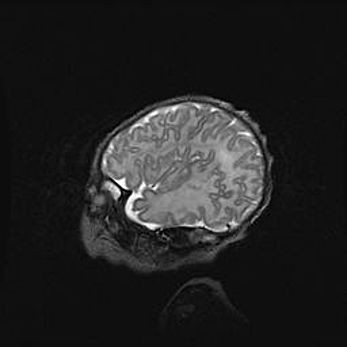

Неполная лизэнцефалия (пахигирия). Открытая гидроцефалия.

Возраст: 17 дней

Вес: 3110 г

Пол: мужской

Окружность головы: 33,5 см

Срок гестации: 35-36 недель

Лизэнцефалия—недоразвитие корковой пластинки и мозговых извилин в результате нарушения миграции нейронов коры. Поверхность мозговых полушарий гладкая. Микроскопически выявляется отсутствие нормальных слоев коры и скопление групп нейронов в подкорковом белом веществе.

Пахигирия—уменьшение числа вторичных извилин. В пораженном полушарии нервные клетки образуют толстый недифференцированный слой с неправильно расположенными нервными волокнами и группами гетеротопных клеток. Нервные клетки незрелые. Белое вещество истончено. При этом нередко аномально развит корково-спинномозговой путь.